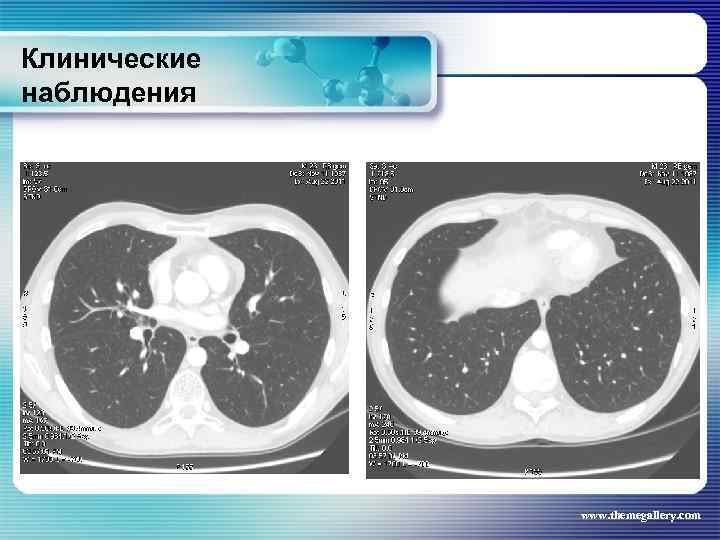

Клинические наблюдения Больной Б. , 1990 г. р. С лета 2008 года увеличены лимфатические узлы на шее. Не обследовался. В течение полугода нарастание слабости, снижение работоспособности, повышение температуры до 38°С, с ознобами и профузными потами. Госпитализирован по месту жительства, а затем в гематологическое отделение. В отделении 02. 2009 г. выполнена биопсия шейного лимфатического узла: лимфома Ходжкина, смешанно-клеточный вариант. При лабораторном исследовании выраженные признаки биологической активности процесса, резко измененные «печеночные» пробы. При лучевом исследовании (рентгенография, СКТ, УЗИ) выявлены признаки поражения внутригрудных, абдоминальных лимфатических узлов, позвонков. www. themegallery. com

Клинические наблюдения Больной Б. , 1990 г. р. С лета 2008 года увеличены лимфатические узлы на шее. Не обследовался. В течение полугода нарастание слабости, снижение работоспособности, повышение температуры до 38°С, с ознобами и профузными потами. Госпитализирован по месту жительства, а затем в гематологическое отделение. В отделении 02. 2009 г. выполнена биопсия шейного лимфатического узла: лимфома Ходжкина, смешанно-клеточный вариант. При лабораторном исследовании выраженные признаки биологической активности процесса, резко измененные «печеночные» пробы. При лучевом исследовании (рентгенография, СКТ, УЗИ) выявлены признаки поражения внутригрудных, абдоминальных лимфатических узлов, позвонков. www. themegallery. com